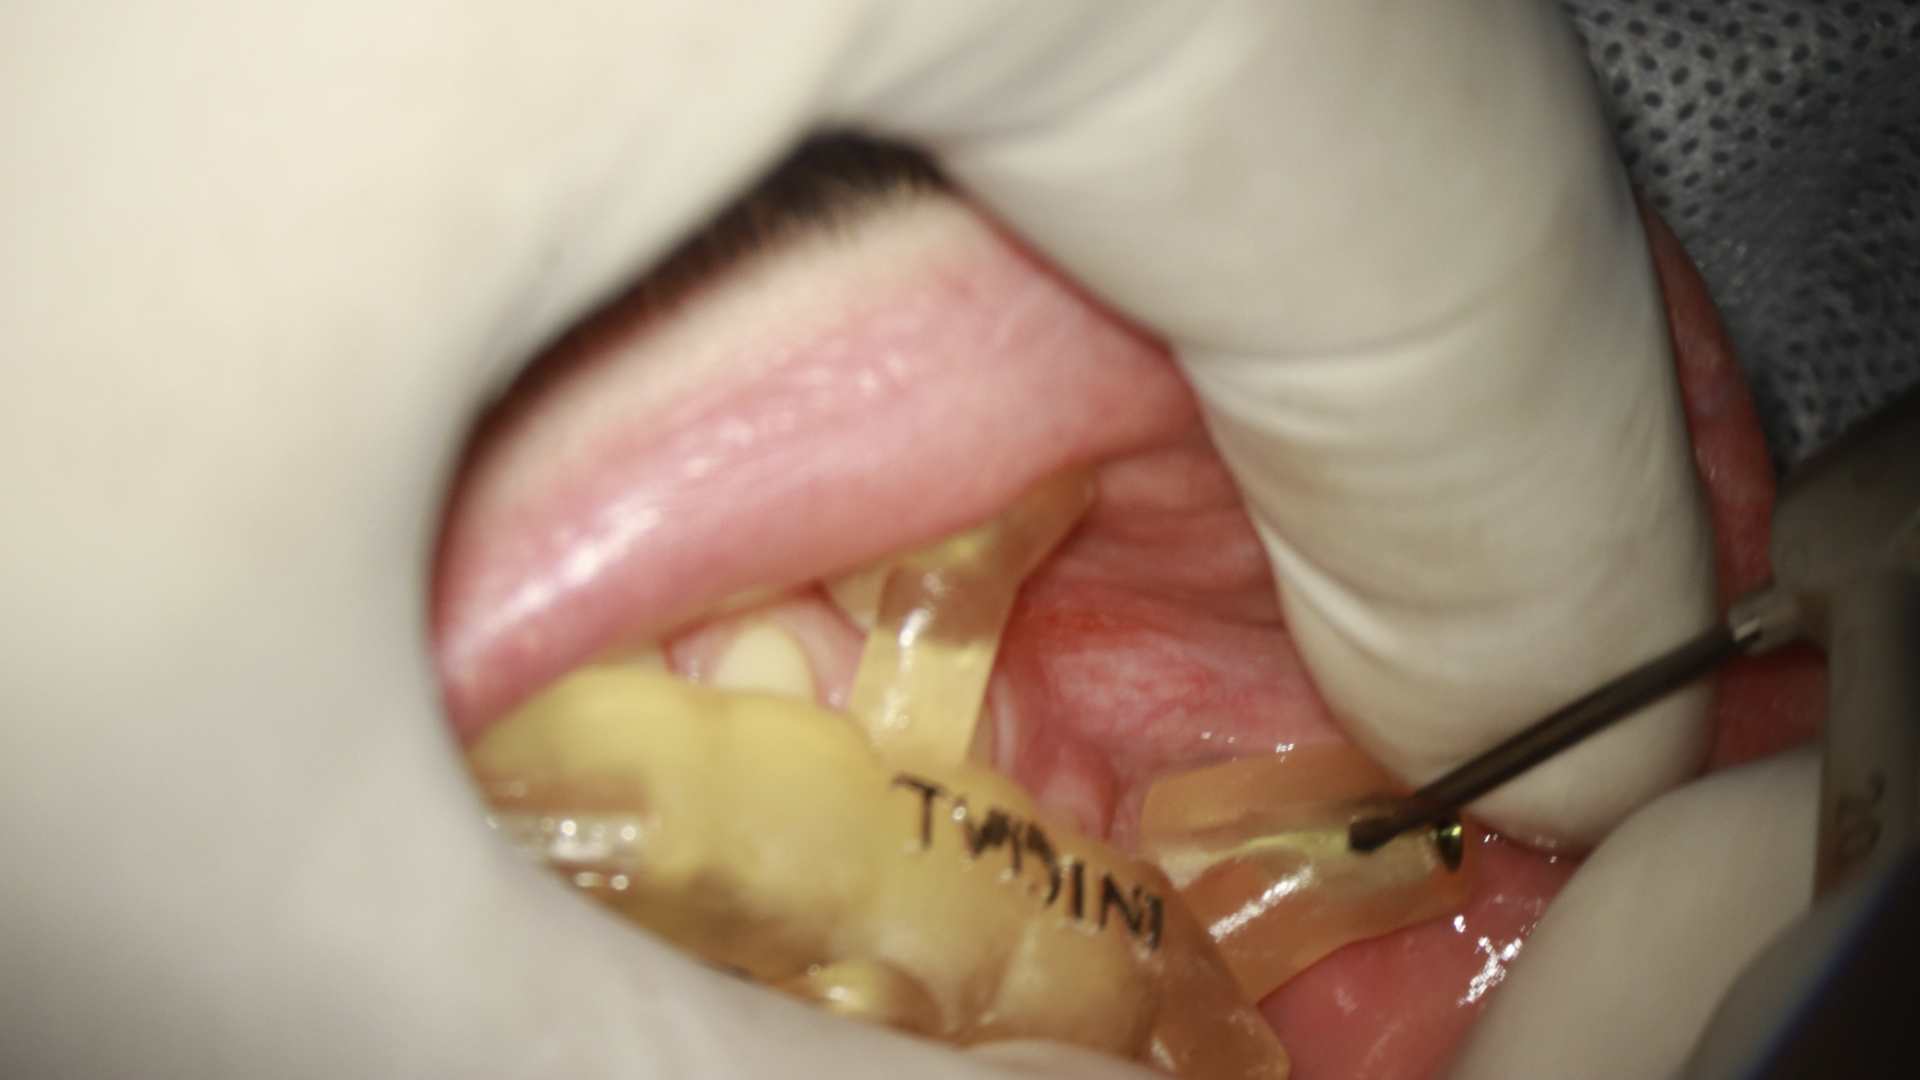

- Prova do endoguide em boca, avaliando a adaptação distal sobre a oclusal dos dentes e também nas janelas que encontramos no guia (figura 4).